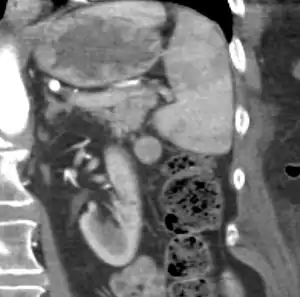

An accessory spleen is a small nodule of splenic tissue found apart from the main body of the spleen. Accessory spleens are found in approximately 10 percent of the population[1] and are typically around 1 centimetre in diameter. They may resemble a lymph node or a small spleen. They form either by the result of developmental anomalies or trauma.[2] They are medically significant in that they may result in interpretation errors in diagnostic imaging[2] or continued symptoms after therapeutic splenectomy.[1] Polysplenia is the presence of multiple accessory spleens rather than one normal spleen.

| CT scan of an accessory spleen (in center of image) between the spleen and left kidney. | |

Accessory spleens may be formed during embryonic development when some of the cells from the developing spleen are deposited along the path from the midline, where the spleen forms, over to its final location on the left side of the abdomen by the 9th–11th ribs. The most common locations for accessory spleens are the hilum of the spleen and adjacent to the tail of the pancreas. They may be found anywhere along the splenic vessels, in the gastrosplenic ligament, the splenorenal ligament, the walls of the stomach or intestines,[3][4] the pancreatic tail,[5][6] the greater omentum,[7][8] the mesentery,[9] the renal fossa,[10][11] or the gonads and their path of descent.[12] The typical size is approximately 1 centimeter, but sizes ranging from a few millimeters up to 2–3 centimeters are not uncommon.[2]

If splenectomy is performed for conditions in which blood cells are sequestered in the spleen, failure to remove accessory spleens may result in the failure of the condition to resolve.[1] During medical imaging, accessory spleens may be confused for enlarged lymph nodes or neoplastic growth in the tail of the pancreas,[5] gastrointestinal tract, adrenal glands or gonads.[2]